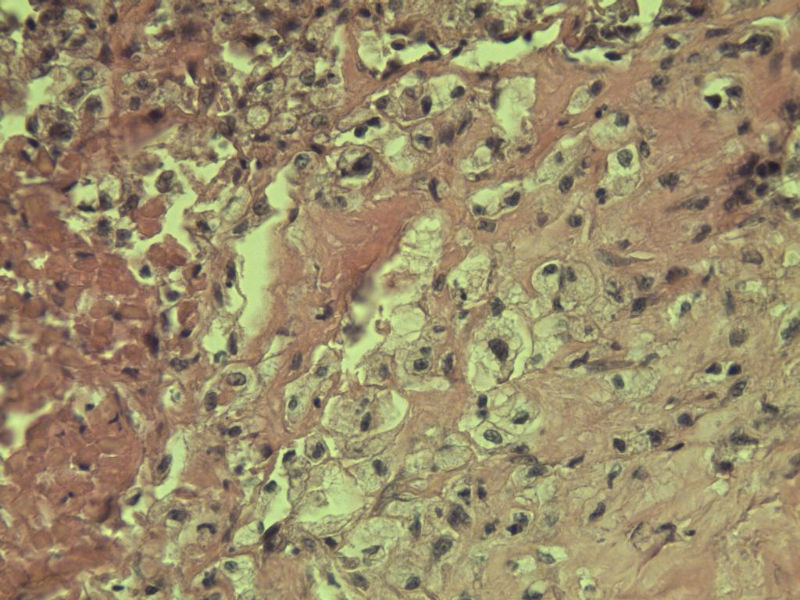

女 70岁 右颈部 头皮 多发皮下结节      取颈部部分结节送检 灰白小组织 1 块,直径 0.4 cm。 请问这个是什么?

肿瘤细胞大,上皮样,核空泡状,核仁明显,胞质嗜酸性或透明。

考虑:恶性黑色素瘤?

近心型上皮样肉瘤?

软组织透明细胞肉瘤?

上皮样多形性脂肪肉瘤?

等免疫组化标记!

此片染色欠佳,取材或切面也有问题,加大了诊断的难度,恶黑确实需要考虑,但其他一些转移癌也需要排除,比如肺癌之类的,还是期待免疫组化!